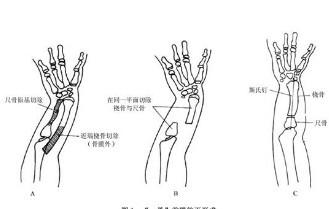

smith骨折

628健康网为您分享有关smith骨折的症状,smith骨折的治疗方法,smith骨折的预防知识,smith骨折的症状图片,smith骨折吃什么药,smith骨...